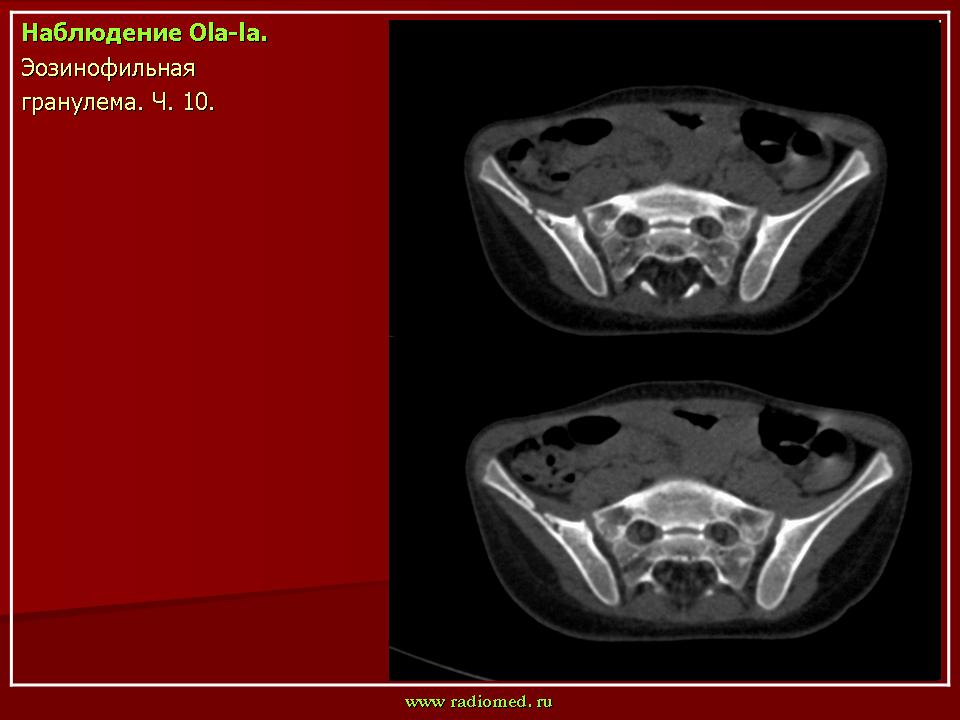

Продолжение.

1.gi_.slayd14.jpg2.gi_.slayd15.jpg3.gi_.slayd16.jpg1.gis_.slayd15.jpg2.gis_.slayd16.jpg3.gis_.slayd17.jpg4.gis_.slayd18.jpg5.gis_.slayd19.jpg6.gis_.slayd20.jpg7.gis_.slayd21.jpg8.gis_.slayd22.jpg9.gis_.slayd23.jpg